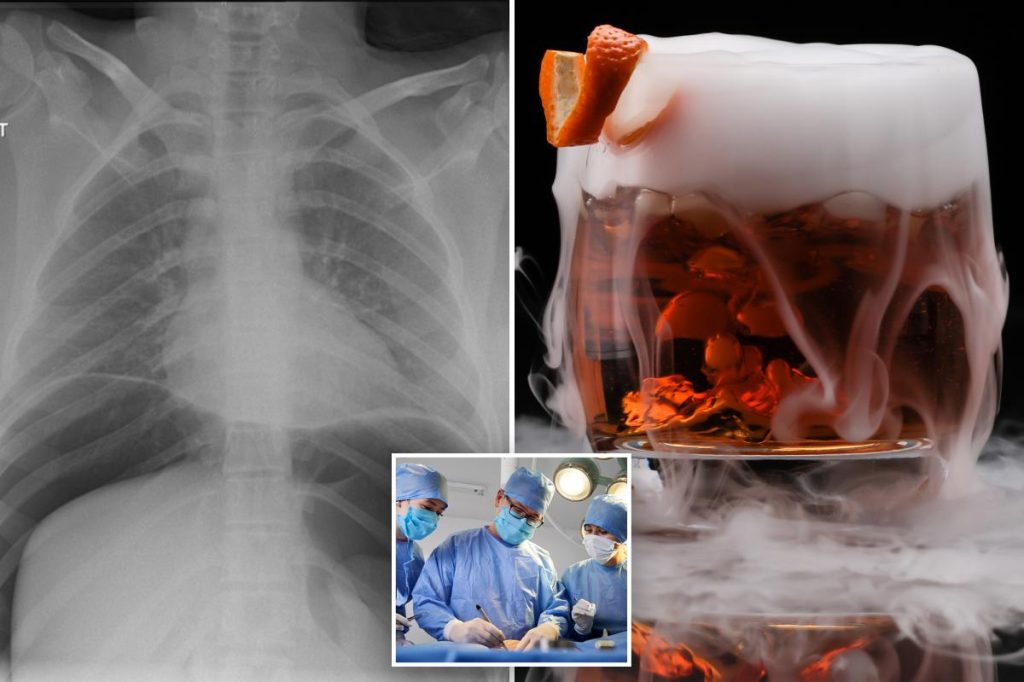

تُثير المشروبات التي تظهر معها أبخرة ملحوظة قلقًا متزايدًا بين الخبراء، حيث تُشير تقارير إلى مخاطر صحية جسيمة مرتبطة باستخدام النيتروجين السائل في تحضيرها. وقد أدت هذه المشروبات، التي غالبًا ما تُقدم كعناصر جذابة بصريًا في الحانات والمطاعم، إلى حالات طوارئ طبية تتراوح بين الحروق الباردة وصولًا إلى تمزق المعدة، بل وحتى الوفاة في بعض الحالات.

عندما يبتلع الشخص النيتروجين السائل، فإنه يتبخر بسرعة في المعدة، مما يؤدي إلى زيادة حجم الغاز بشكل كبير. يمكن أن يتسبب هذا التمدد السريع في الضغط على جدران المعدة، مما يؤدي إلى تمزقها في الحالات الشديدة. وفقًا لتقارير طبية، يمكن أن يؤدي تمزق المعدة إلى تسرب الغاز إلى تجويف البطن، مما يسبب تضخمًا شديدًا، وفشلًا تنفسيًا، ونزيفًا داخليًا، وهي حالات تهدد الحياة.

بالإضافة إلى ذلك، يمكن أن تتسبب درجة حرارة النيتروجين السائل المنخفضة للغاية (-319 درجة فهرنهايت تقريبًا) في تجميد الأنسجة، مما يزيد من تفاقم الضرر. في حالة الفتاة البالغة من العمر 18 عامًا التي نُقلت إلى المستشفى في لانكستر بالمملكة المتحدة، تطلب علاجها إزالة جزء من معدتها (استئصال المعدة) بسبب الضرر الذي لحق بالأنسجة.